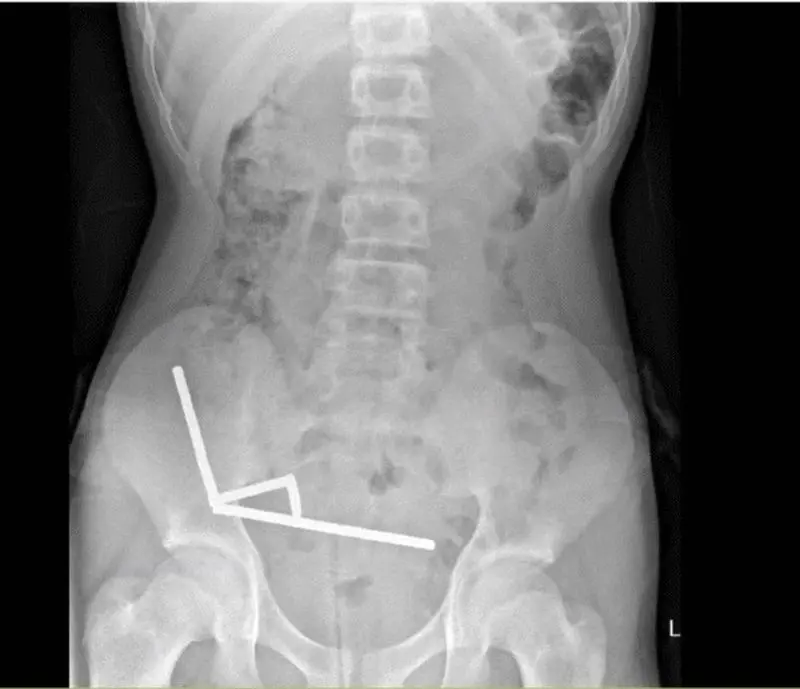

تصاویر رادیولوژی، چهار زنجیره بلند از آهنرباها را در بخش‌های جداگانه روده نشان داد. این ذرات فلزی کوچک درون بدن به هم متصل شده و باعث انسداد، پارگی و مرگ بخشی از بافت روده بر اثر فشار مغناطیسی شدند. در نهایت، پزشکان ناچار شدند بخشی از روده را خارج کنند.به گفته تیم درمان، وضعیت عمومی این نوجوان پس از عمل جراحی رضایت‌بخش است و او پس از هشت روز بستری، از بیمارستان مرخص شد.

زنجیره‌های آهنربا که در شکم نوجوان نیوزیلندی یافت شدند.